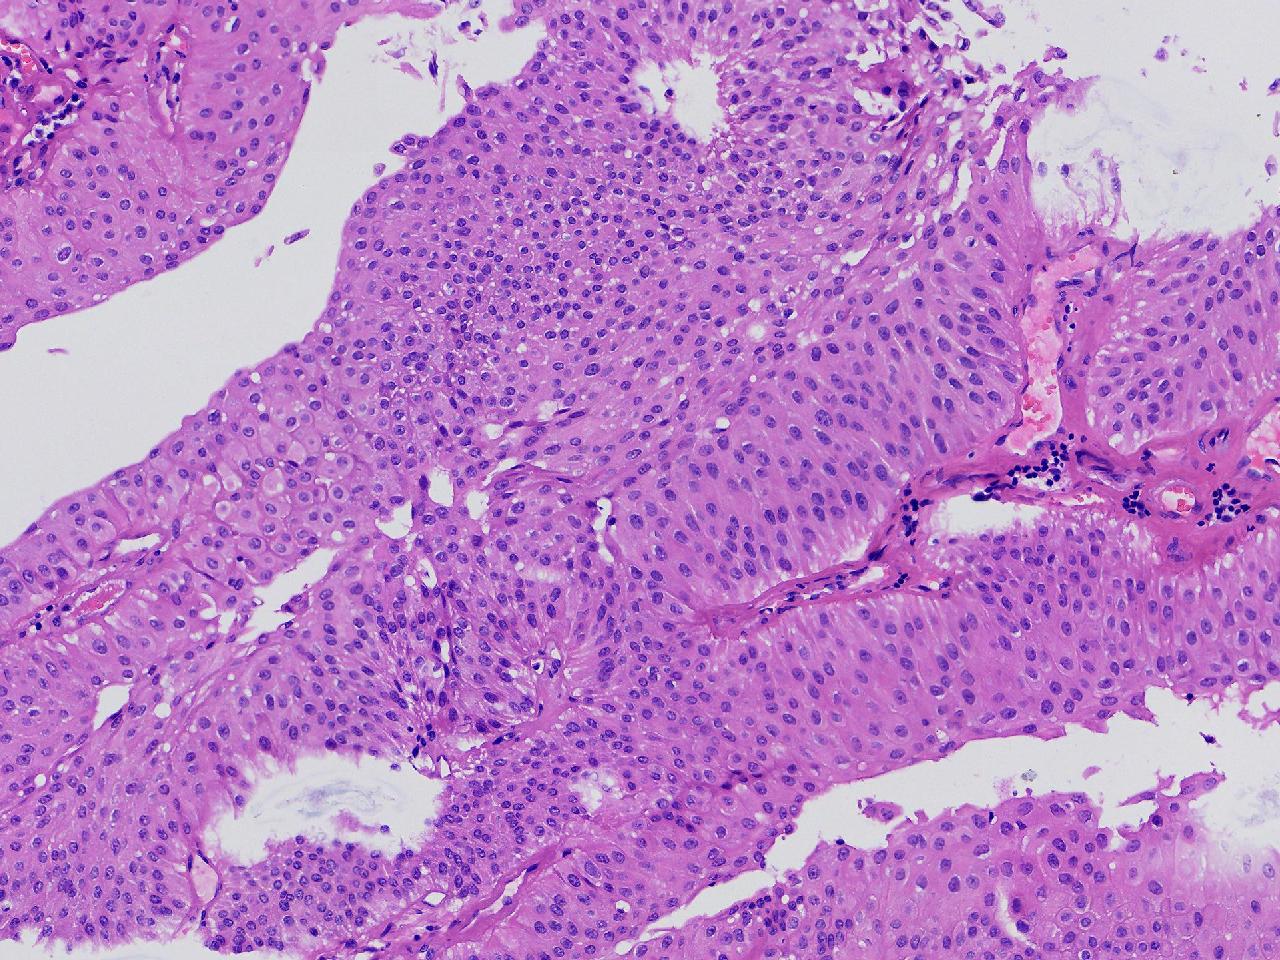

男,79岁,膀胱肿物。

膀胱肿物

灰白色不整形软组织多块,2X1X1厘米。

考虑:乳头状尿路上皮癌

乳头状尿路上皮癌,低级别。

这几张图片上没有看到明确的浸润。